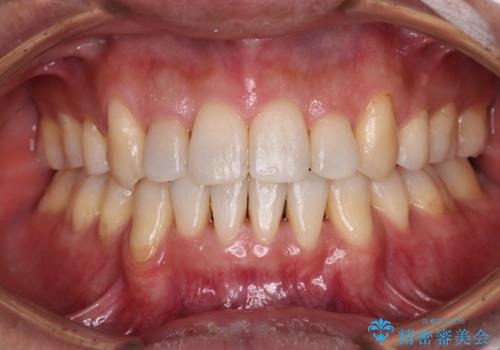

50代女性 八重歯を矯正治療 歯並びの中等度のがたつき

マウスピース矯正が煩わしい ワイヤー装置での非抜歯矯正

担当医 藤巻太一朗